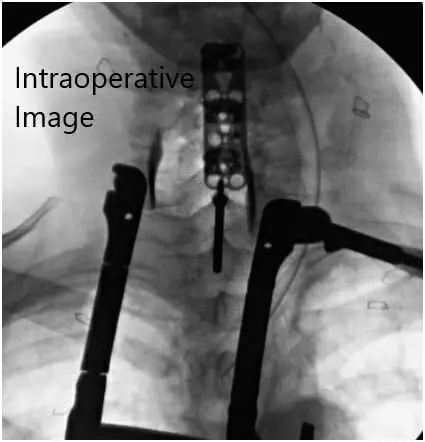

Intraoperative fluoroscopic images

Intraoperative fluoroscopic images 2

Intraoperative fluoroscopic images.

We applied lordosis using the handheld lordotic bender to the plate and using fluoroscopy to ensure the appropriate sizing of the plate.  The cervical plate was placed anteriorly and 4.2 x 16 mm screws were then used in the C3, C4, C5, and C6 vertebral bodies.  We obtained fluoroscopy throughout to ensure proper trajectory for the screws.